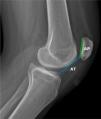

Se han descrito múltiples métodos para cuantificar la altura patelar en radiografías. En la actualidad el índice más utilizado en la literatura es el de Caton-Deschamps (ICD)1,17 (fig. 2), que consiste en el cálculo de la relación entre la distancia desde el punto inferior de la superficie articular de la rótula hasta la meseta tibial anterosuperior (AT) y la longitud de la superficie articular de la rótula (AP). Este índice presenta el beneficio de no verse afectado con las osteotomías de distalización de la tuberosidad anterior de la tibia (TT), permitiendo así evaluar la corrección postoperatoria de la altura patelar. Para este índice, valores >1,2 son considerados como patela alta3.

En la actualidad no se ha demostrado una clara concordancia entre las medidas de la altura patelar en radiografías, TC y RM, viéndose estas últimas afectadas por el grado de flexión de la rodilla, la contracción del cuádriceps y la modalidad de imagen, por lo que su uso debe realizarse con cautela.